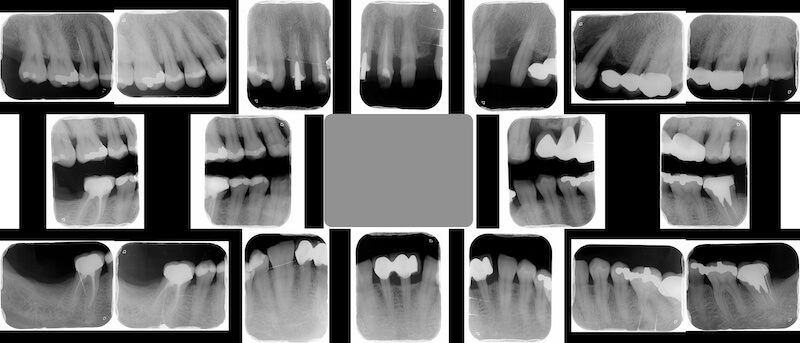

經過全口初步檢查以及X光片的檢查,我的診斷是全口中度慢性牙周病。治療牙周病過程中我會搭配顯微鏡和水雷射,也就是『顯微水雷射牙周病治療』。不過在牙周治療前,我們也要先把上述的兩個會加重牙周病的問題一併考量,治療才會有效果。

Ms.H 是屬於第一種並且血壓已控制良好的高血壓患者。因此我們會在拆除她的舊假牙之後再開始進行全口牙周治療。拆除假牙後發現右上的側門齒是齒質不足的殘留牙根,因此預計在之後治療牙周病時同時拔除該患齒。

拆除舊假牙換上臨時假牙之後,開始進入牙周病的療程。我們會先將治療前口內狀況完整記錄,詳細分析每一顆牙齒的牙周狀況。